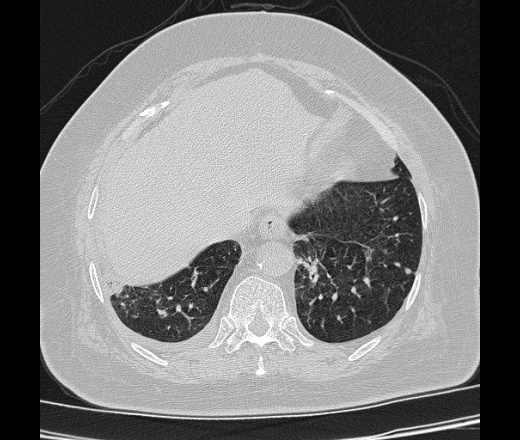

Медицинская диагностика: фотографии, иллюстрирующие облитерирующий бронхиолит